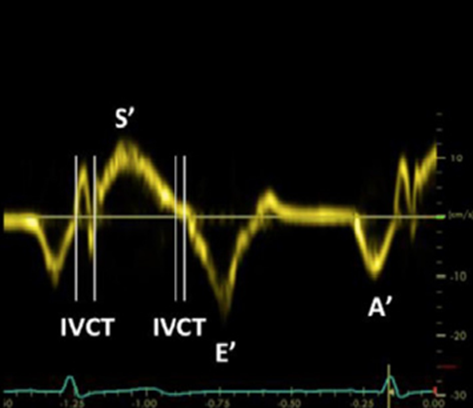

Detecting reduced RV function or strain is a key component of the quantitative evaluation. The two methods described here both evaluate the systolic movement of the tricuspid valve annulus at the RV free wall in the A4C view. This movement is considered a surrogate for contractility of the RV. The first method of evaluating RV strain is tissue doppler imaging (TDI). With an A4C view, the TDI doppler gate is placed in the tissue of the lateral tricuspid annulus, then a tracing generated. (Figure 4) The positive deflection, which represents maximum annular velocity, is referred to as s’. If s’ is less than 9.5, there should be concern for RV strain.

Figure 4. TDI of tricuspid annulus for evaluation of RV strain.